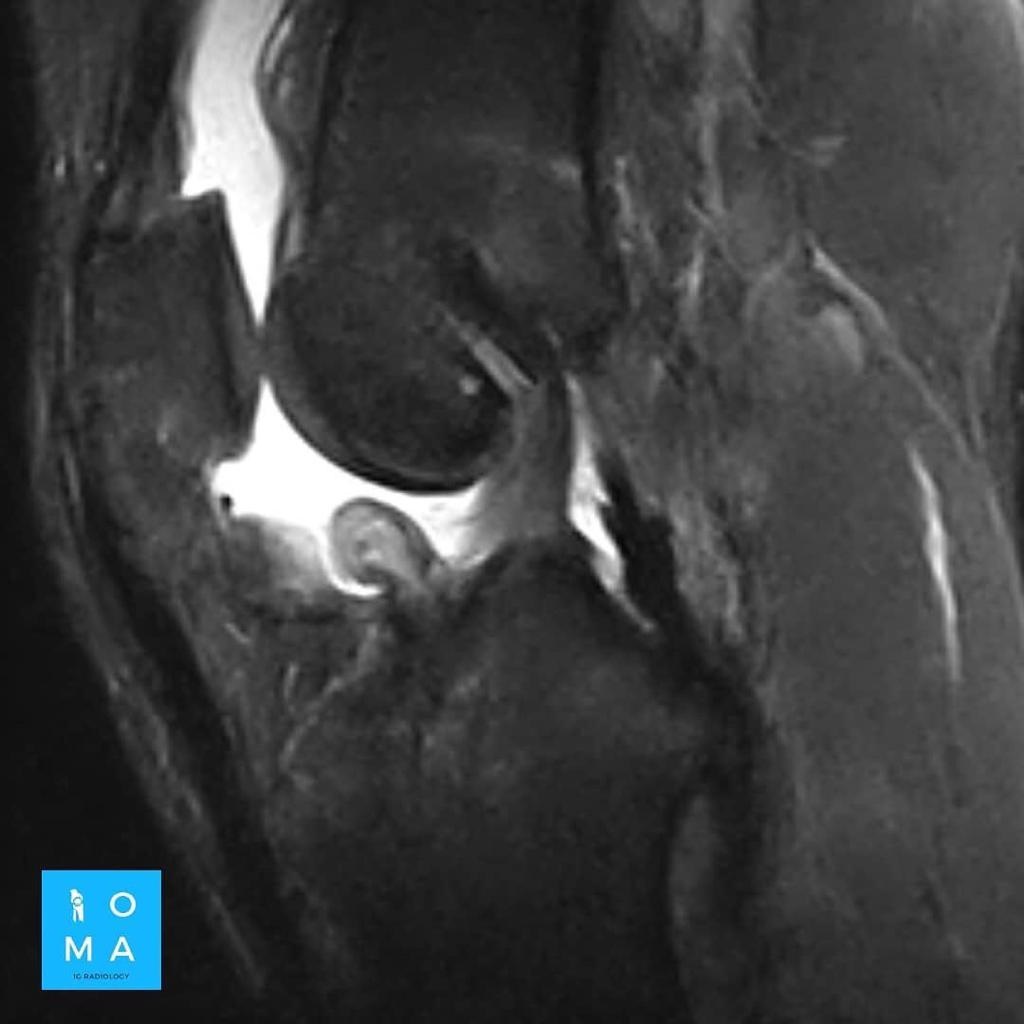

RM en la rodilla operada